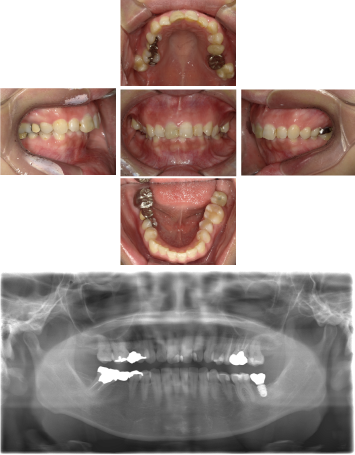

30代 女性 奥歯 インプラントGBR

| 年代・性別 | 30代・女性 |

| 治療回数 | 1回 ※術前治療・検査除く |

| 治療期間 | 5ヶ月 |

| 料金 | ¥60,000(税込) |

GBR(Guided Bone Regeneration:骨再生誘導法)とは、インプラント治療において、骨の厚みや高さが足りない場合に行う歯槽骨を再生する方法です。骨量不足の患者様でも、骨造成を行うことでインプラントの埋入に必要な骨の高さや厚みが得られます。 GBR(再生誘導法)は、骨が痩せて十分な骨量が確保できない患者様に、骨の再生によってインプラントの埋入を可能にする治療方法の一つです そのような骨が欠損した部分では、骨を作る「骨芽細胞」よりも、骨にならない「線維芽細胞」の方が増殖しやすいという特徴があります。そのためGBRでは、骨形成の妨げになる繊維芽細胞の侵入を防ぐため、骨を増やしたい部分を「メンブレン」という人工膜で覆い、その中に自家骨や人工の骨補填材を詰めて骨芽細胞の増殖を促します。 |

| 副作用 | 術後に腫れ・痛みが出る可能性がある。 |